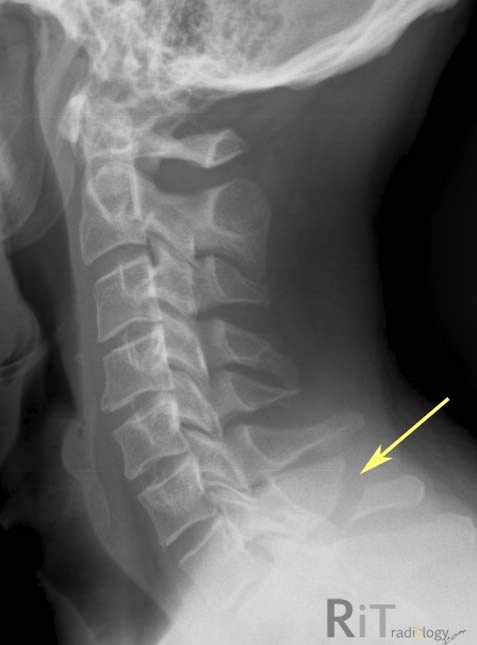

The type of fracture seen here:

What is a blow out fracture?